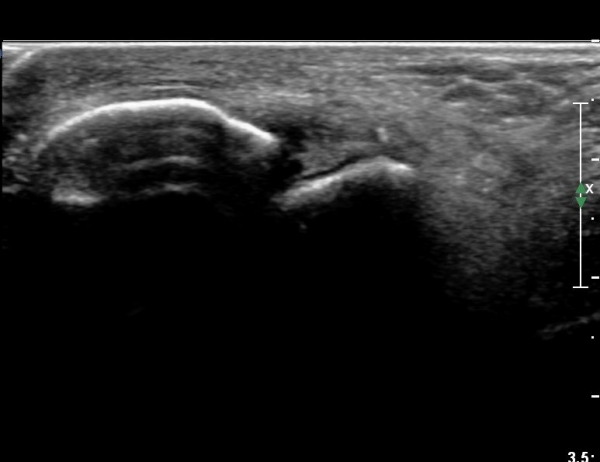

Àü°ÅºñÀÎ´ë ºÎÇϰ˻翡¼­ ÀδëÆÄ¿­ ºÎÀ§°¡ ¹ú¾îÁö°í °Å°ñÀÌ ¾ÕÀ¸·Î ´Ü°ÜÁö´Â ¼Ò°ßÀ» º¸ÀÓ(»çÁø 3, 4, ÷ºÎ µ¿¿µ»ó).